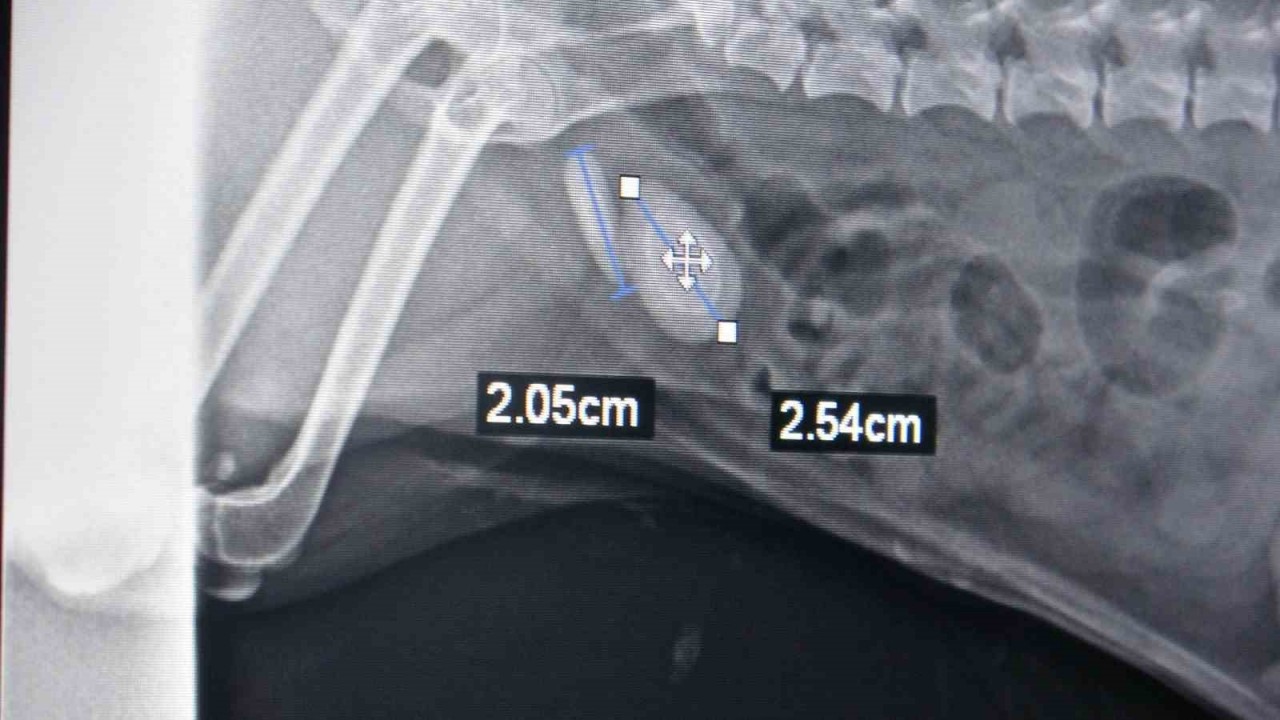

Tokat’ta bir evcil hayvan sahibi köpeğinin idrar yapamaması, idrardaki renk değişiklikleri, idrarda kan olması, idrara gitme isteği ama idrarını yapamaması şikayetleriyle veteriner hekime başvurdu. Yapılan muayenelerin ardından köpeğin idrar kesesinde taş olduğu tespit edildi. Yapılan operasyonla köpeğin idrar kesesindeki üç taş çıkarıldı. Ameliyatı gerçekleştiren veteriner hekim Muhammet Ahmet Gülden, "Evcil hayvan idrar yapamama şikayetiyle kliniğimize başvurdu. Yaptığımız ultrason muayenesinde taş tespit ettik. Ondan sonra yaptığımız röntgen muayenesi ile taşı tam olarak teşhis edip, ameliyat kararı aldık. Toplam teşhis ettiğimiz taş iki taneydi ama ameliyat yaptığımızda üç tane taş çıkardık. 2 buçuk, 2 ve 1 santimetrelik bu taşları sistotomi ameliyatıyla aldık. Ameliyat olan evcil hayvan terrier ırkı, 7 veya 8 yaşında bir köpek. Sürekli tuvalete gidip idrarını yapamama şikayetiyle geldi. İdrar kesesinin yankısı, idrarda taş kristaller, kum, enfeksiyon hastalıkları, bunlar da benzer şikayetlerle olabiliyor. Tabii hasta sahibinin bunu anlayabileceği en önemli belirti idrardaki renk değişiklikleri, idrarda kan olması, idrara gitme isteği ama idrarını yapamaması. Evcil hayvan sahiplerinin bu durumla karşılaştıkları zaman ilk yapması gereken şey fazla zaman kaybetmeden bir veteriner hekime başvurmaları olmalıdır. Hayvanın uzun süre idrarını yapamaması böbrek yetmezliğine sebebiyet veriyor. Böbrek yetmezliği ölüm durumuna kadar götüreceği için hayati risk oluşturuyor. Bazı hayvanlarda yatkınlık var. Bazı ırklarda taş oluşması ile alakalı yatkınlıklar var. Onun dışında beslenme bozuklukları gibi olgular da etkili olabilir. Erkek hayvanlar dişi hayvanlara göre taş ve idrar kesesi yangısına daha yatkındır. Kediler ve köpekler, özellikle kısırlaştırılmış olan hayvanlar mutlaka kısır kedi mamaları yemeleri gerekiyor. Bunlar dışında hazır su tüketmeleri de önemli bir durumdur. Çeşme suyundan ziyade hazır su daha sağlıklı olacağından, bunlara dikkat etmeleri daha iyi olur. Şu an ameliyat olan köpek iyi durumda, idrarını yapabiliyor" dedi.